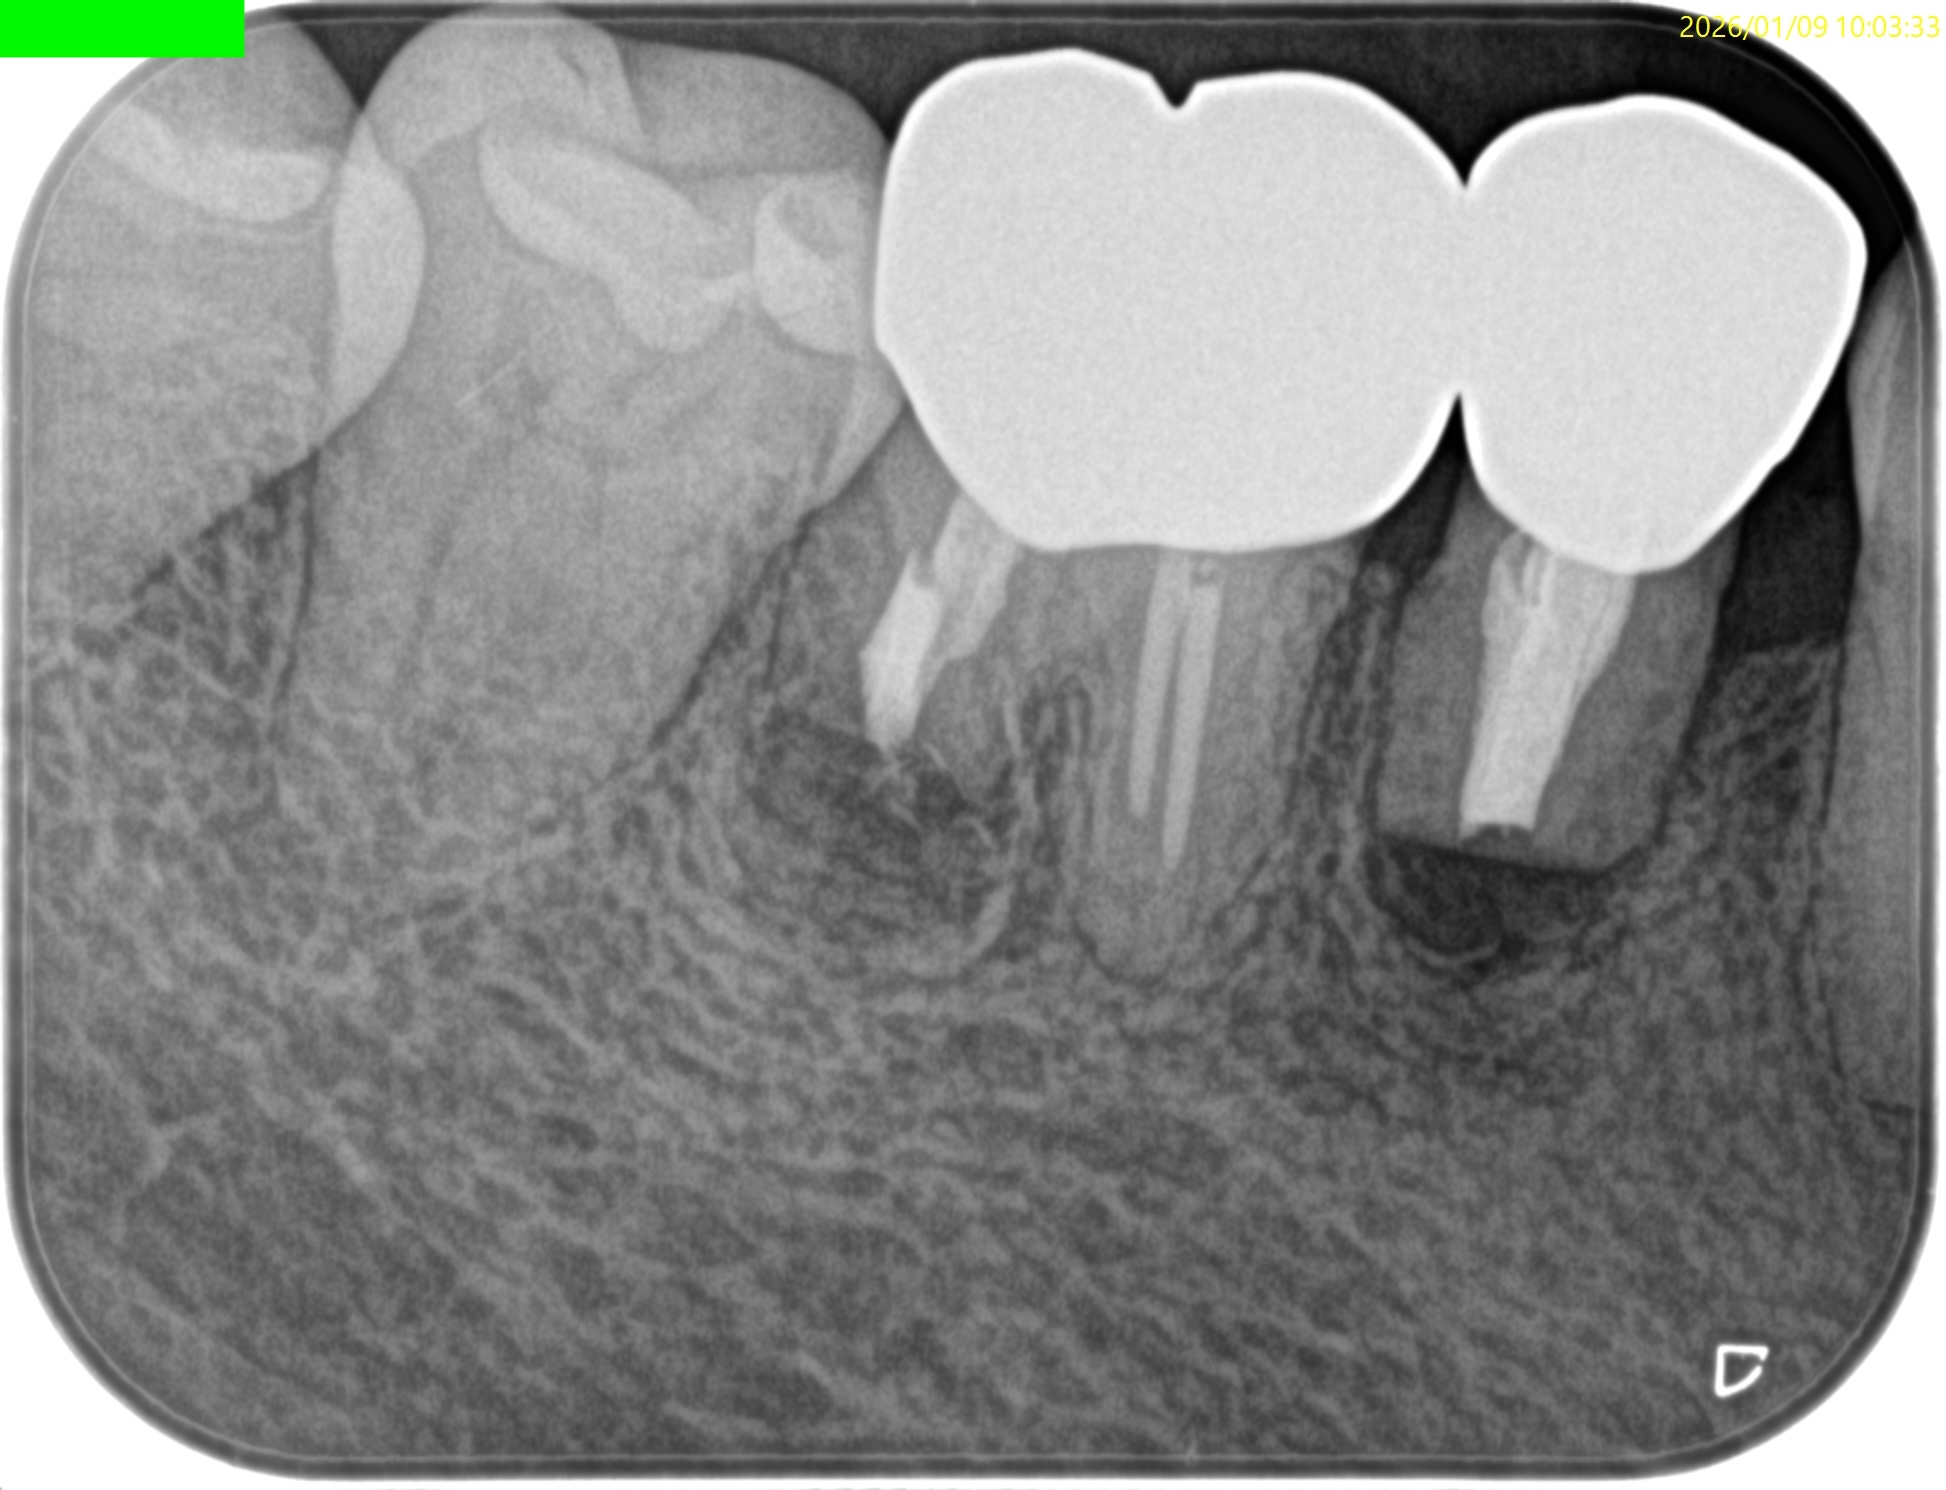

#30 D Apicoectomy 3M recall(2026.1.9)

#30の術前の圧痛が消失していた。

PAの感じもだいぶ変わっていた。

CBCTも撮影している。

歯槽骨も回復傾向だ。

このまま経過を見ていく。